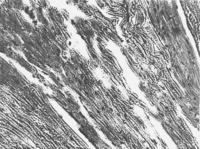

При исследовании сердца установлено, что эпикард и эндокард имеют свойственное строение (Рис. 4 ).

Основная часть миокарда, рабочая сердечная ткань, сформирована из миоцитов, прочно соединенных своими концами и образующих многочисленные анастомозы. Зоны контакта миоцитов имеют вид одиночных темноокрашенных прямолинейных или ступенчатых полосок, расположенных перпендикулярно длины оси клеток. Миоциты содержат 1-2 светлых ядра овальной формы, имеющих центральное расположение. Поперечная исчерченность, обусловленная строением миофибрилл, отчетливо выражена. Миоциты окружены тонковолокнистой соединительной тканью (эндомизий миокарда), содержащие многочисленные умеренно кровенаполненые капилляры, обеспечивающие процессы микроциркуляции.

Атипичные миоциты (проводящие) более светлые, имеют неправильную форму и поперечный диаметр в 2-3 раза больше, чем диаметр сократительных миоцитов.

Рисунок 3. Сердце. Группа № 1 (контроль).

Эпикард и эндокард имеет свойственное им строение (Увел. 400).